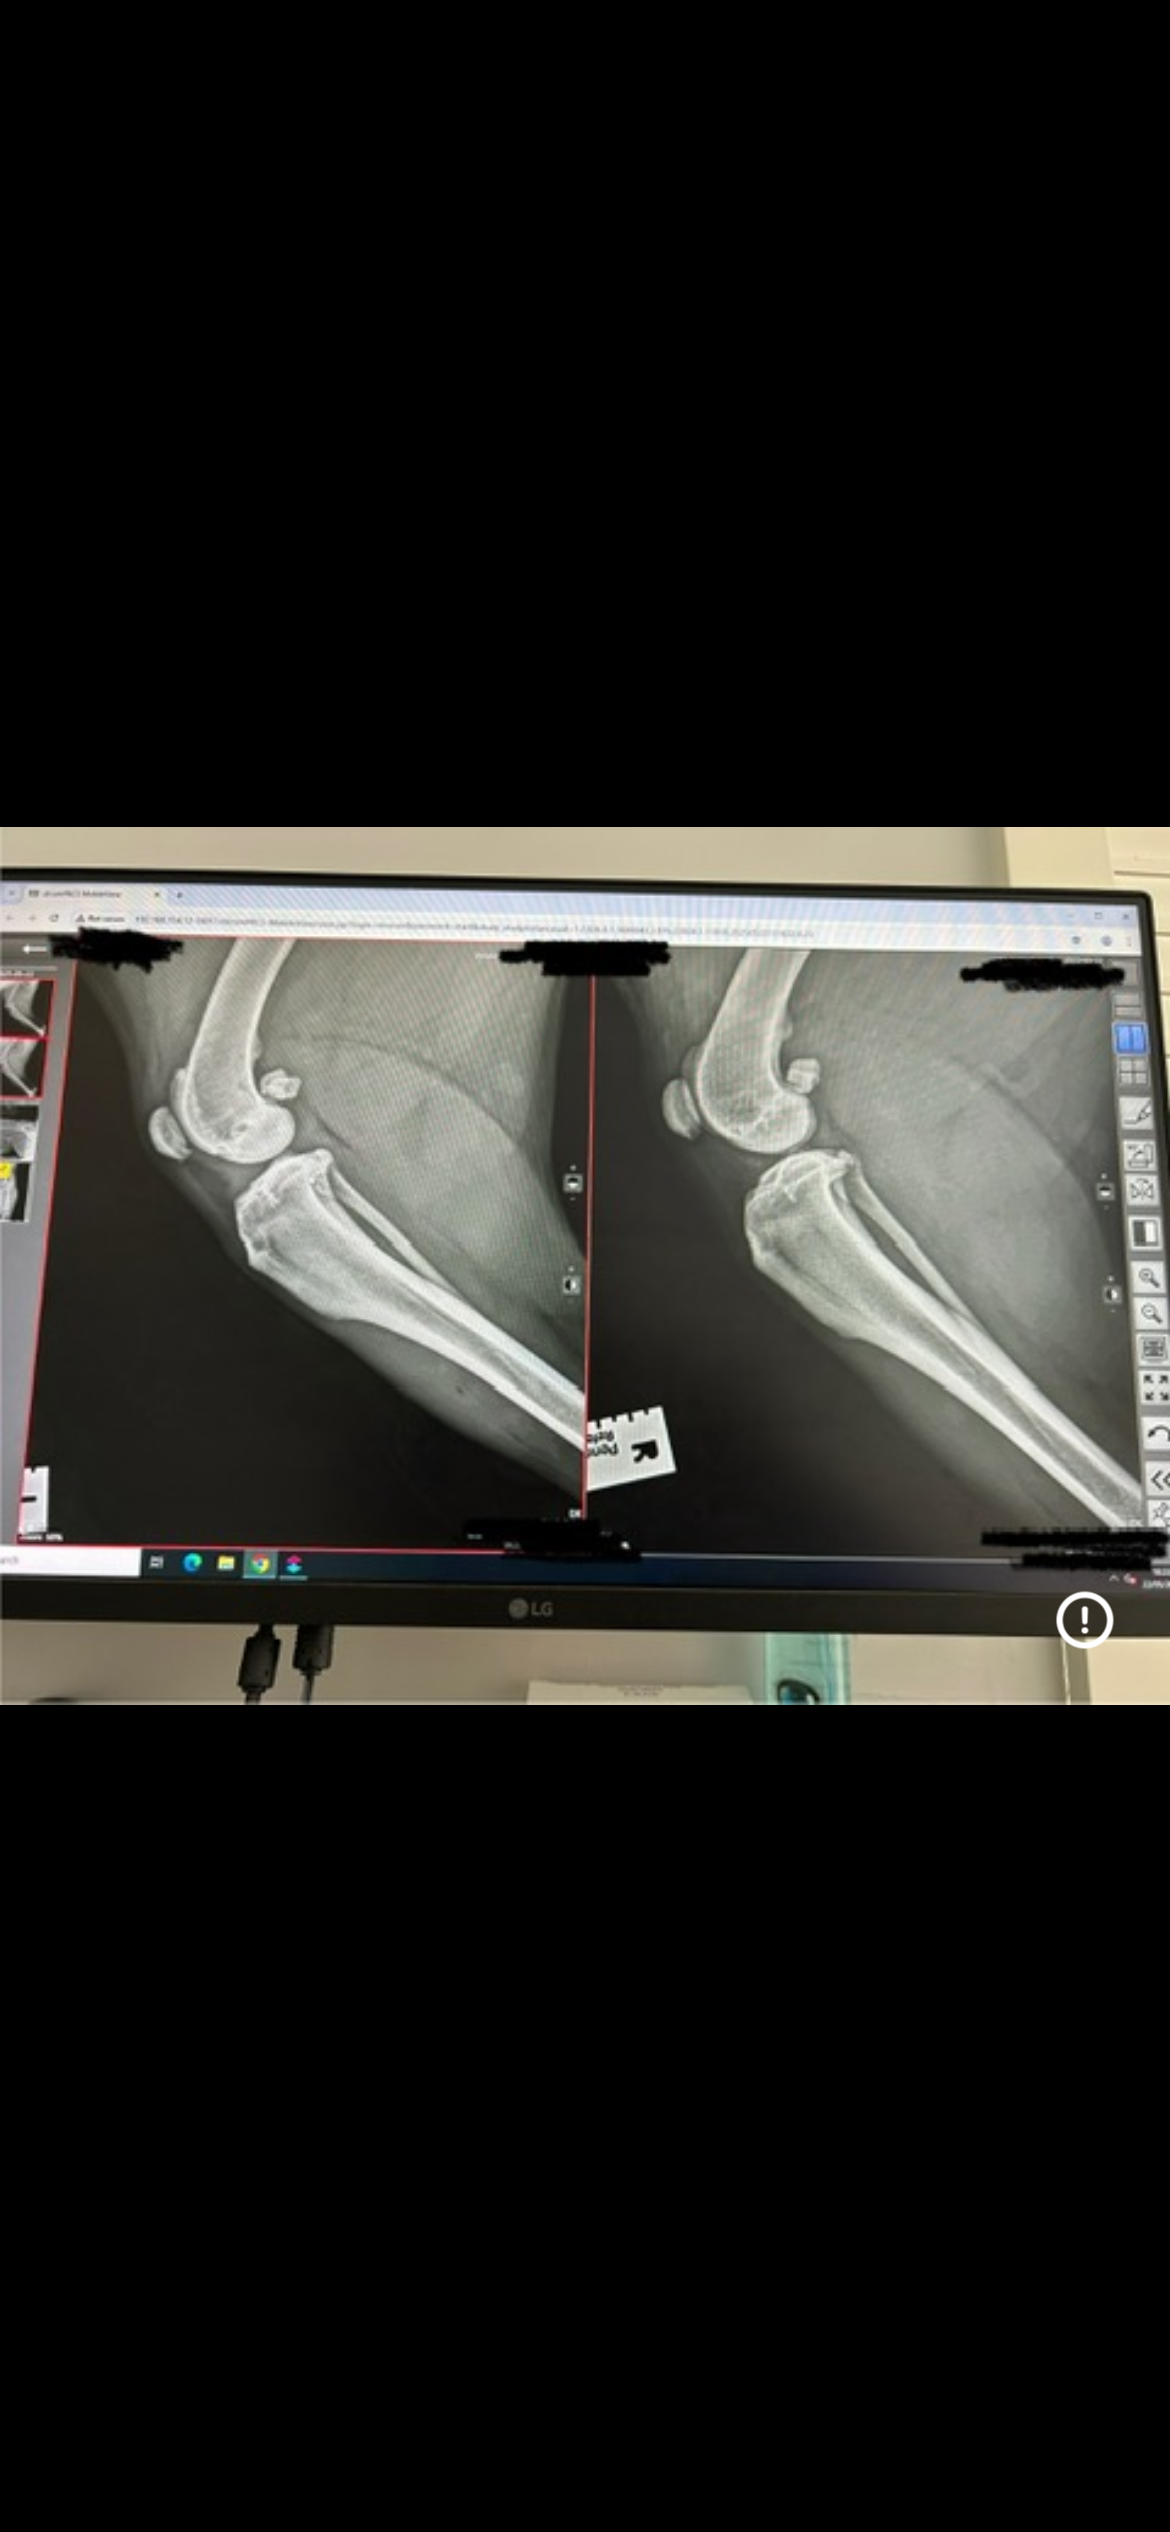

I have hip dysplasia and osteoarthritis, and my x-rays showed that the ligament in my left back leg is torn. The vets said that without TPLO surgery, I will never be able to walk properly again.